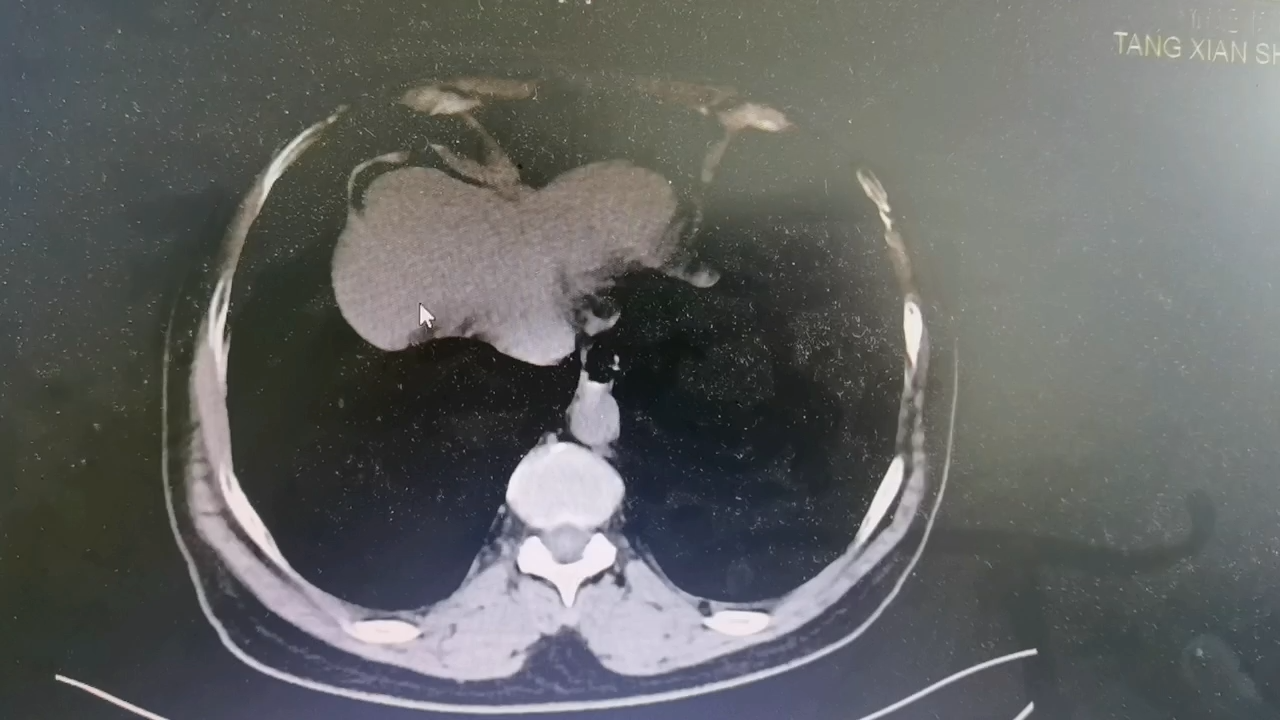

【检查】:CT检查提示右侧腰部切口疝复发。

【临床诊断】:右侧腰部切口疝